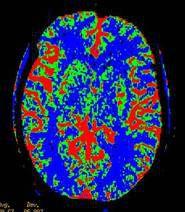

腦的重量占體重的2%-3%,但其所需要的血流量則占心輸出量的15%-20%。腦血流量是指每100g腦組織在單位時間內通過的血流量。本節著重闡述各種生理狀態下的全腦血流量。

全腦血流量正常人安靜狀態下腦血流量腦血流量因測定方法不同,正常值有所差異。在安靜情況下,一個一般身材的年輕人每分鐘的全腦血流量為700-770ml,約合每分鐘50-55ml/100g。當平均半球血流量減少到每分鐘25-30ml/100g時,可發生精神錯亂,甚至意識喪失。神經功能衰減的臨界血流量大約是每分鐘18ml/100g。